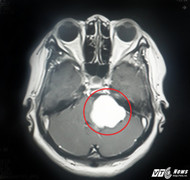

Bệnh viện Xuyên Á (TP.HCM) vừa phẫu thuật thành công ca tách khối u màng não to như quả bóng bàn ra khỏi mạch máu thần kinh của nam bệnh nhân.